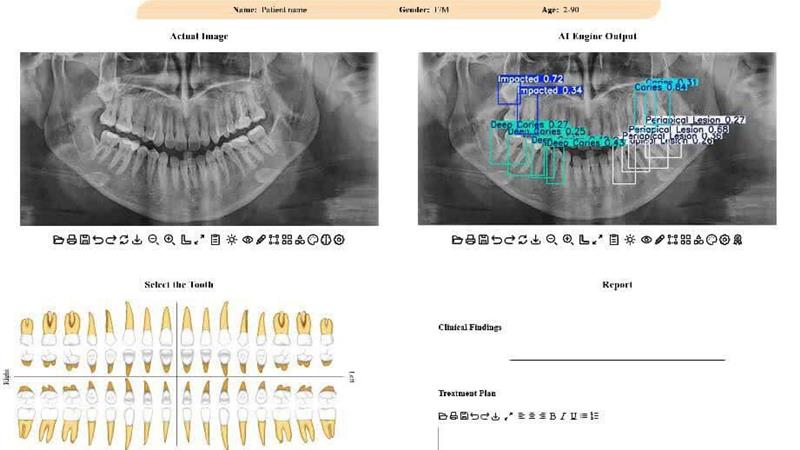

استاد دانشکده مهندسی برق و کامپیوتر دانشگاه تهران با بیان اینکه در این پژوهش جدید محققان تلاش کردهاند تا این چالش را با کمک فناوری حل کنند، افزود: برای این منظور یک سامانه تشخیصی مبتنی بر هوش مصنوعی طراحی شده است که این سامانه، معماری پیشرفته شبکه عصبی به نام YOLOv11 است که آموزش آن بر روی یک مجموعهداده عمومی انجام شده است. این مدل قادر است بهصورت خودکار، محل دقیق ضایعات و ناهنجاریها را در تصویر شناسایی کرده و احتمال درستی تشخیص خود را نیز اعلام کند.

ظروفی یکی از نقاط قوت این پژوهش را کاربردی شدن پژوهش در قالب یک اپلیکیشن وب، عنوان کرد و گفت: یکی از نقاط قوت این پژوهش، کاربردی بودن آن است. این مدل در قالب یک اپلیکیشن تحت وب پیادهسازی شده تا دندانپزشکان و رادیولوژیستها بتوانند به سادگی از آن استفاده کنند. این سامانه با مشخص کردن محل دقیق مشکلات، به پزشک در اولویتبندی و تصمیمگیری سریعتر کمک میکند.